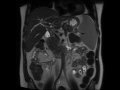

Primary Sclerosing Cholangitis (PSC)

MRI images demonstrate beading, irregularity, and multifocal structuring of the biliary tree, compatible with the patients known primary sclerosing cholangitis (PSC)